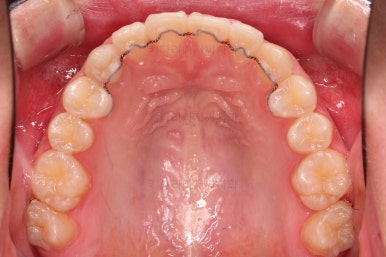

동래교정치과 첫 단계로 악궁확장 장치를 했습니다.

악궁확장 이 후 브라켓을 부착합니다.

이번 환자분이 선택하신 장치는 엠파워 클리어라고 하는 자가결찰 세라믹 장치인데요.

철사를 스스로(자가) 묶을 수(결찰) 있는 뚜껑이 달린 세라믹 성분의 장치입니다.

대표적인 장치가 클리피씨 장치이며 클리피는 일본회사, 동래교정치과 키다리아저씨치과가 쓰는 엠파워는 미국회사라는 차이가 있고 큰 틀에서는 동일한 계열의 장치입니다.